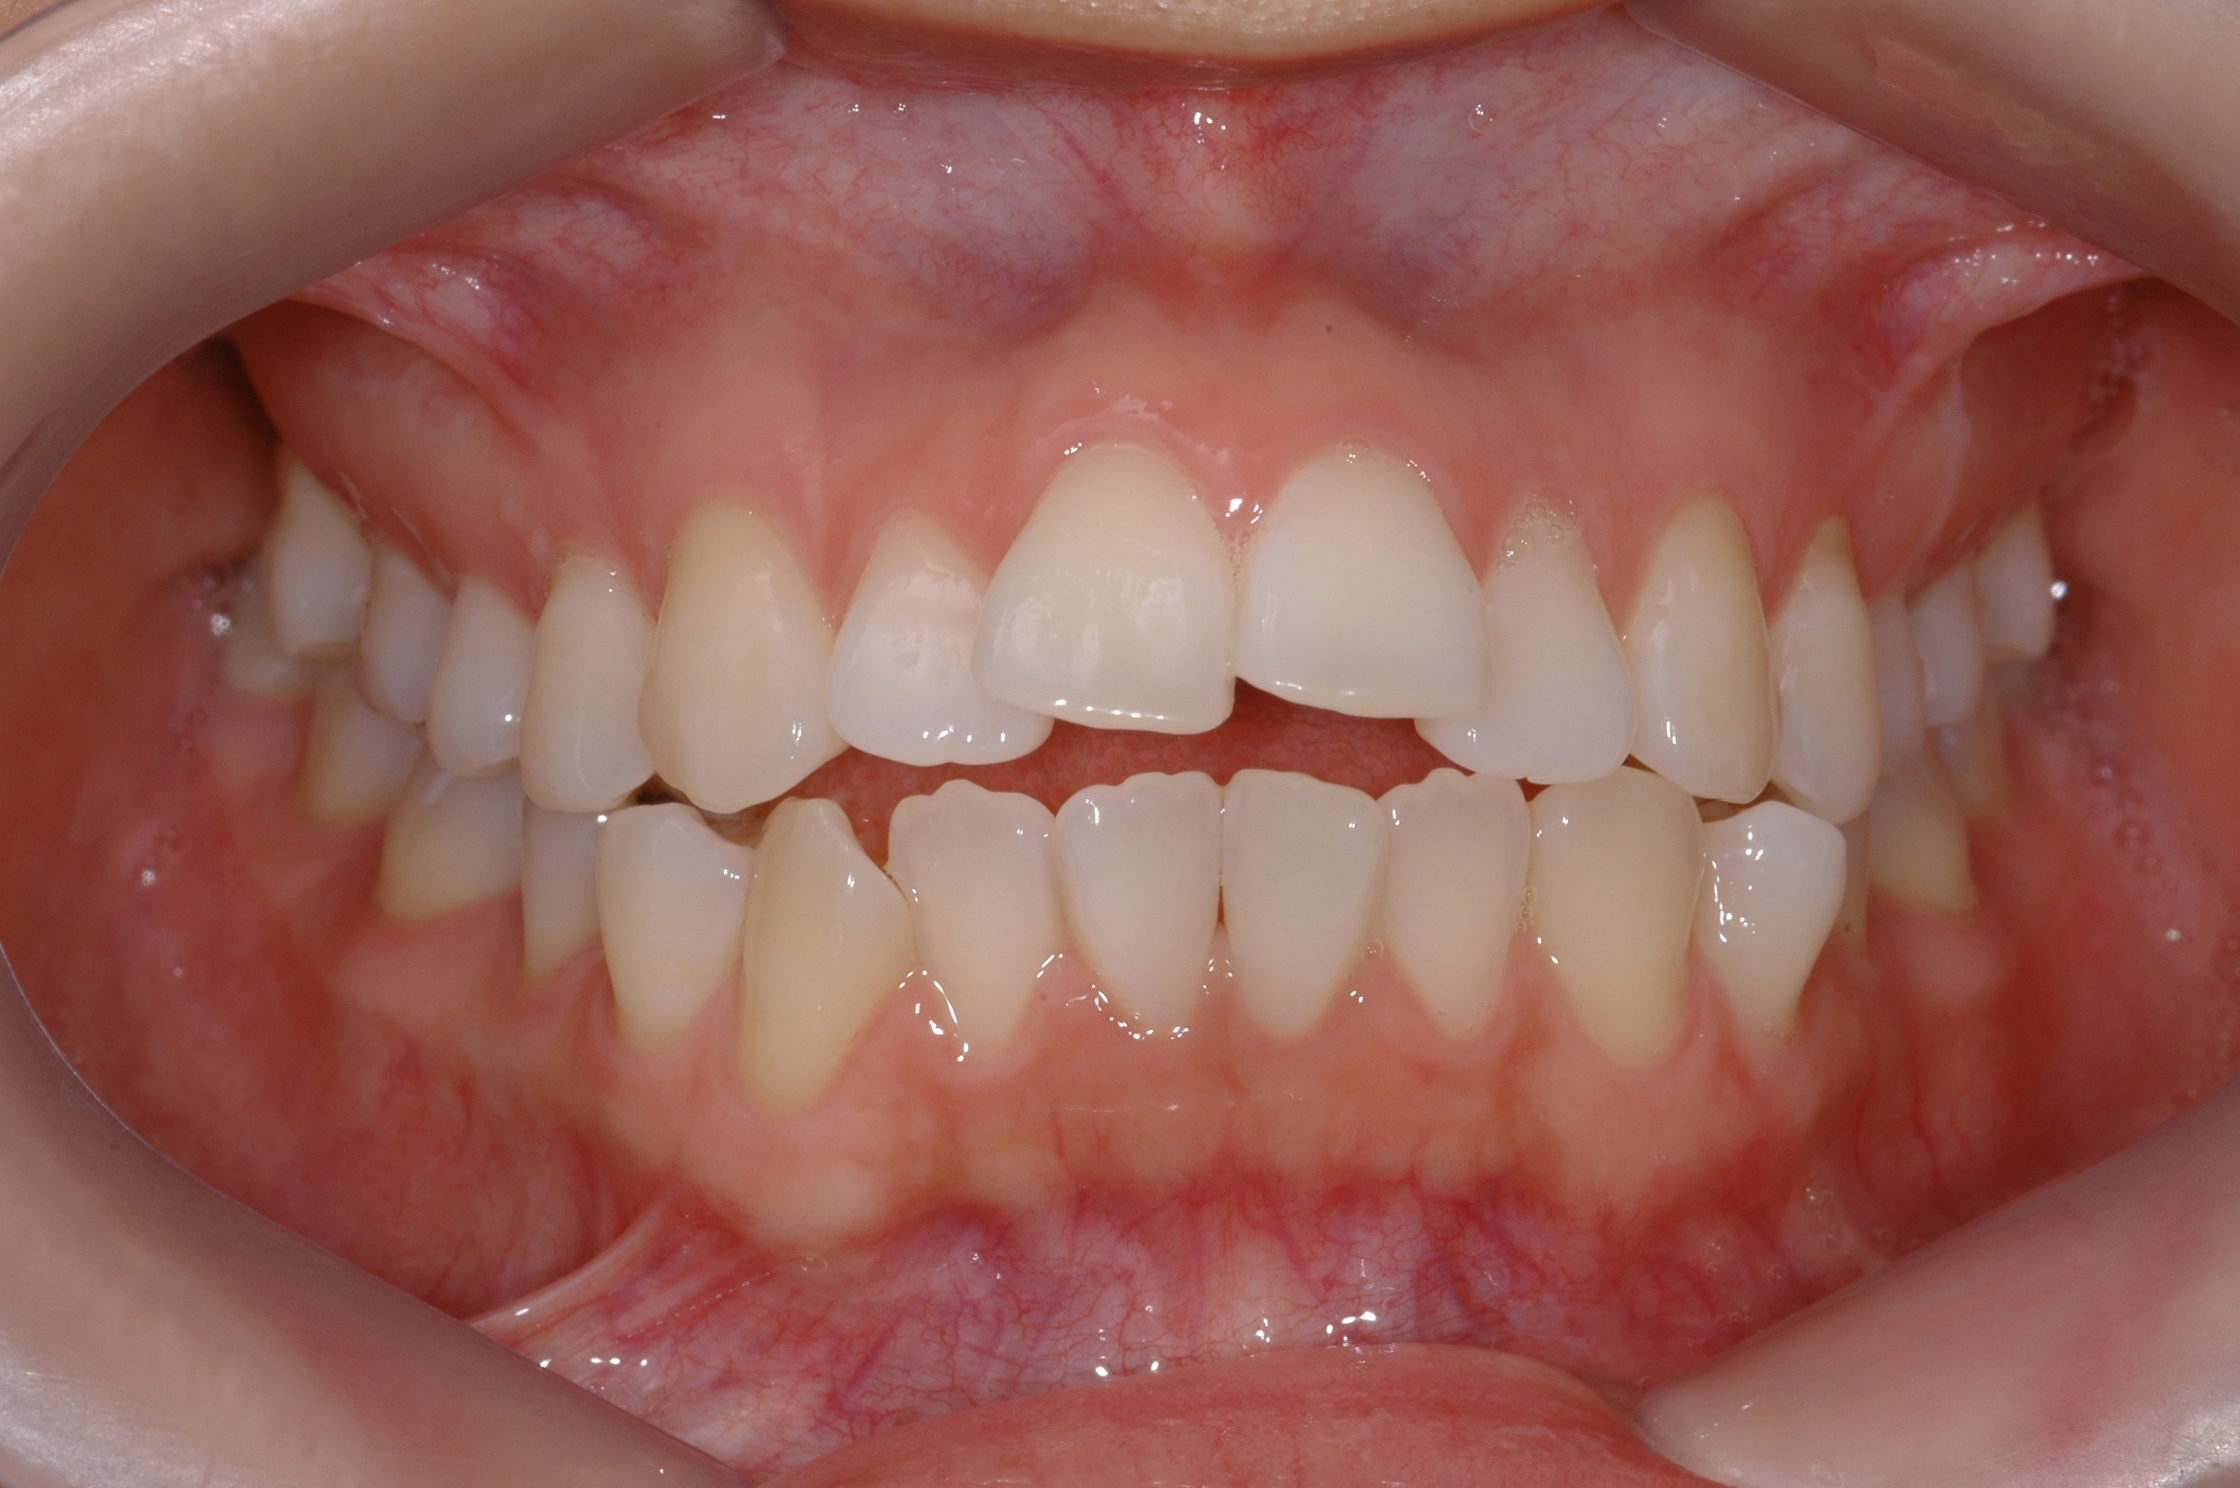

치료 전 사진입니다.